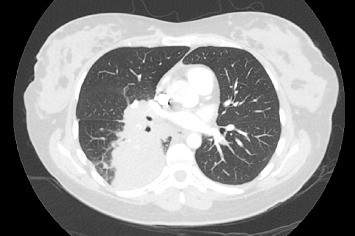

由于靶向治疗的安全性数据有限,妊娠期间癌基因驱动的非小细胞肺癌(NSCLC)的管理面临着独特的挑战。间变性淋巴瘤激酶(ALK)重排非小细胞肺癌是一种罕见的疾病,但越来越多的人认识到它存在于年轻女性中,包括怀孕期间。在这里,我们报告一例37岁的女性在她的第一次怀孕期间被诊断为转移性alk重排NSCLC,她开始使用alectiinib。在此之后,她成功地进行了第二次怀孕,同时接受了alectinib治疗(在妊娠6-10周期间暂停,以避免器官发生的关键时期)。两次怀孕都产生了健康的婴儿,没有并发症或发育迟缓的迹象。本病例强调了多学科方法的重要性,包括肿瘤学、母胎医学、临床遗传学、产科医学和产科,以平衡孕产妇癌症控制和胎儿健康。虽然临床前研究表明阿勒替尼有致畸风险,但这一病例和其他报道的病例表明,在仔细计划的情况下,妊娠期间使用阿勒替尼是安全的。本例胎盘病理检查未发现恶性细胞,母体疾病得到控制。随着靶向治疗延长晚期非小细胞肺癌的生存期,更多的患者可能会考虑怀孕,这强调了需要强有力的证据来指导治疗决策。该病例提供了越来越多的证据,支持alk重排NSCLC患者使用alectinib等靶向治疗来管理妊娠的可行性,同时强调了对暴露后代进行长期随访的重要性。

The management of oncogene-driven non-small cell lung cancer (NSCLC) during pregnancy presents unique challenges due to limited safety data on targeted therapies. Anaplastic lymphoma kinase (ALK)-rearranged NSCLC is a rare but increasingly recognized entity in young women, including during pregnancy. Here, we report the case of a 37-year-old woman diagnosed with metastatic ALK-rearranged NSCLC during her first pregnancy, who was commenced on alectinib. Following this, she had a successful second pregnancy whilst being treated with alectinib (withheld during weeks 6-10 of gestation to avoid the critical period of organogenesis). Both pregnancies resulted in healthy infants with no complications or evidence of developmental delays. This case highlights the importance of a multidisciplinary approach involving oncology, maternal-fetal medicine, clinical genetics, obstetrics medicine, and obstetrics to balance maternal cancer control and fetal health. While preclinical studies of alectinib suggest teratogenic risks, this and other reported cases demonstrate its potential for safe use during pregnancy with careful planning. Pathological examination of the placenta in our case revealed no malignant cells, and maternal disease remained controlled. As targeted therapies extend survival in advanced NSCLC, more patients may contemplate pregnancy, emphasizing the need for robust evidence to guide treatment decisions. This case contributes to the growing body of evidence supporting the feasibility of managing pregnancy in patients with ALK-rearranged NSCLC using targeted therapies like alectinib, while underscoring the importance of long-term follow-up for the exposed offspring.